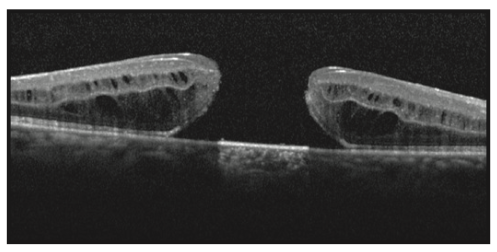

O diagnóstico para detecção do buraco de mácula é feito através de exames que ampliam essa região permitindo observar o grau de comprometimento são eles: mapeamento de retina, retinografia, angiografia de retina e tomografia de coerência óptica (OCT).

O exame mais importante nessa situação será o de OCT, que ira nos mostrar o tamanho do buraco e outros sinais de bom ou mal prognóstico de fechamento do buraco macular.